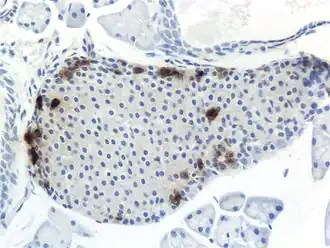

![]() b: Hetzelfde PP-celrijke gebied geprojecteerd op de alvleesklier in een anatomische positie (in vivo). |

PP-cellen (pancreas polypeptidecellen), vroeger ook wel gammacellen (γ-cellen) of F-cellen genoemd, zijn cellen in de eilandjes van Langerhans van de alvleesklier. Hun belangrijkste rol is het helpen synthetiseren en reguleren van de afgifte van pancreas polypeptide (PP), waarnaar ze vernoemd zijn. De eilandjes, waar PP-cellen zich bevinden, werden in 1869 ontdekt door een Duitse pathologisch anatoom en wetenschapper, Paul Langerhans. PP-cellen helpen bij de opbouw van de alvleesklier, maar zijn het kleinst in verhouding tot de andere cellen in de eilandjes. De verhoudingen kunnen variëren afhankelijk van welke dieren worden bestudeerd, maar bij mensen vormen PP-cellen minder dan 2% van de populatie eilandjescellen.[1] In de verrijkte zone van het haakvormig uitsteeksel (kop alvleesklier) vormen PP-cellen 50-90% van het celvolume van het eilandje.[2]

De alvleesklier vervult meerdere functies bij zoogdieren. Hij speelt een rol in het spijsverteringsstelsel en het endocrien systeem, waardoor het een orgaan en een zeer belangrijke klier is.[3] PP-cellen bevinden zich meestal in de eilandjes van Langhans en behoren tot de zeldzamere alvleesklierceltypen.[1] Sommige kleine clusters kunnen ook worden aangetroffen in andere delen van het spijsverteringskanaal, vooral in de dunne darm en de dikke darm.[4][5] Gezien hun locatie in de eilandjes en hun lage populatie, kunnen ze efficiënt reageren op veranderingen in de bloedsuikerspiegel, zenuwimpulsen en chemische signalering via gap junctions of celsignalering. PP-cellen vertonen de hoogste concentratie aan de kop van de alvleesklier.[1]